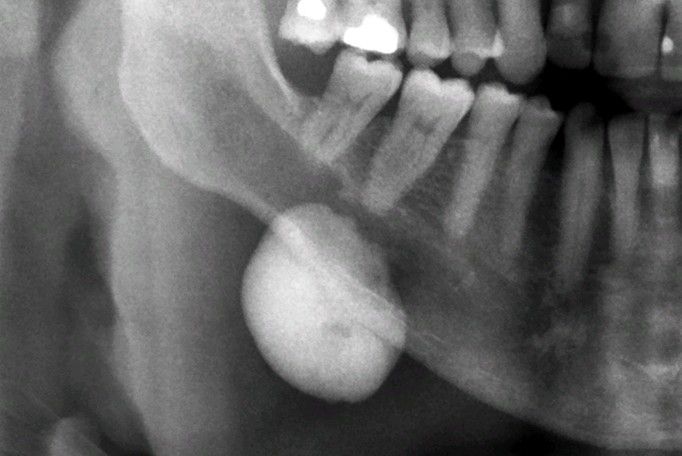

Osteoma

. Panoramic radiograph showing a uniformly sclerotic mass arising from the surface of the posterior mandible.